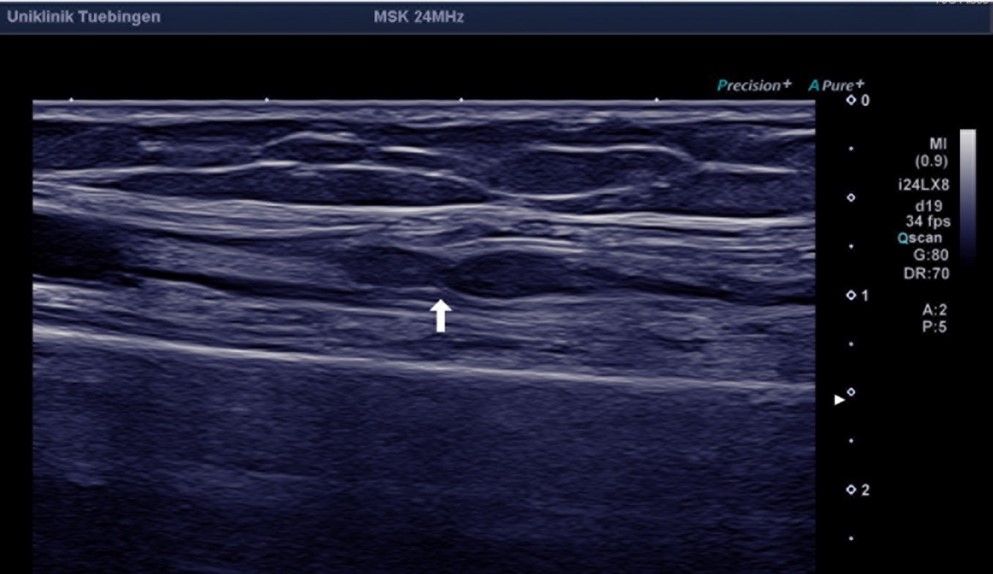

Die neuralgische Amyotrophie ist eine entzündliche Erkrankung, welche sich typischerweise durch plötzlich auftretende Schmerzen (häufig im Bereich der Schulter oder des Arms), gefolgt von einer Lähmung der Muskulatur, äußert. Eine Ursache ist nicht immer sofort erkennbar. Während die Schmerzen mit der Zeit abklingen, können die Lähmungen anhalten und infolge der Entzündungsreaktion narbige Einschnürungen an den betroffenen Nerven entstehen. Die Erkennung dieser Einschnürungen („Konstriktionen“) kann zunächst schwierig sein und erfordert spezielle Untersuchungsmethoden im Sinne einer hochauflösenden Neurosonographie durch erfahrene Neurolog*innen oder einer MR-Neurographie. Sollten sich solche Nervenkonstriktionen bestätigen kann eine operative Therapie gute Ergebnisse erzielen.

Ein lange Zeit weitgehend unbekanntes und weiterhin unterdiagnostiziertes Krankheitsbild stellt die neuralgische Amyotrophie, früher auch Plexusneuritis oder Schulteramyotrophie, dar. Hierbei handelt es sich um eine entzündliche Nervenerkrankung, deren Ursache nicht immer geklärt werden kann. Risikofaktoren stellen eine übermäßige mechanische Beanspruchung (z.B. durch ungewohnte starke körperliche Aktivität), immunologische Auslöser (z.B. Infektionen) oder eine genetische Veranlagung dar. Durch Verbesserungen in der Diagnostik, insbesondere dem hochauflösenden Nervenultraschall sowie der Magnetresonanzneurographie gelingt eine zunehmend bessere bildgebende Darstellung des gesamten Verlaufs peripherer Nerven. Dabei können einerseits entzündlich bedingte Schwellungen der Nerven festgestellt und die Diagnose bestätigt werden.

Die neurologische Akutbehandlung besteht aus schmerzstillenden Mitteln sowie hochdosierten entzündungshemmenden Cortison-Infusionen mit. Häufig bilden sich die Beschwerden darunter nach einigen Wochen wieder zurück. Immer wieder kommt es jedoch zu einem Fortbestehen der Lähmungen. Mithilfe der oben genannten Fortschritte bei bildgebenden Untersuchungen zeigte sich in den letzten Jahren, dass bei diesen Patientinnen und Patienten häufig narbige Einschnürungen der betroffenen Nerven bestehen, (sogenannte uhrglasförmige Nervenkonstriktionen), die den Nerv sogar verdreht erscheinen lassen können („Torsionen“). Bei Vorhandensein solcher Konstriktionen ist in der Regel eine medikamentöse Behandlung nicht weiter erfolgversprechend. Durch eine operative Narbenlösung kann dann in der Regel eine gute Erholung der Nervenfunktionen erreicht werden.